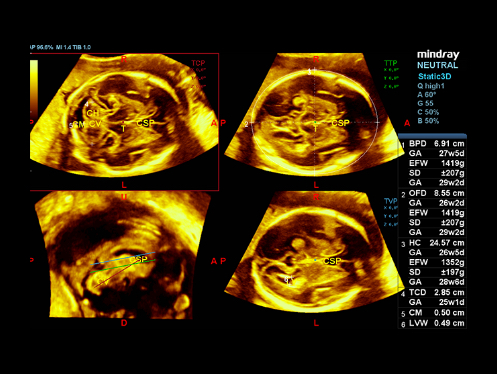

El DC-80A con X-Insight ofrece una solución inteligente excepcional para la atención médica integral de la mujer, desde los exåmenes de fertilidad y prenatales hasta la atención médica posparto.

ImĂĄgenes clĂnicas